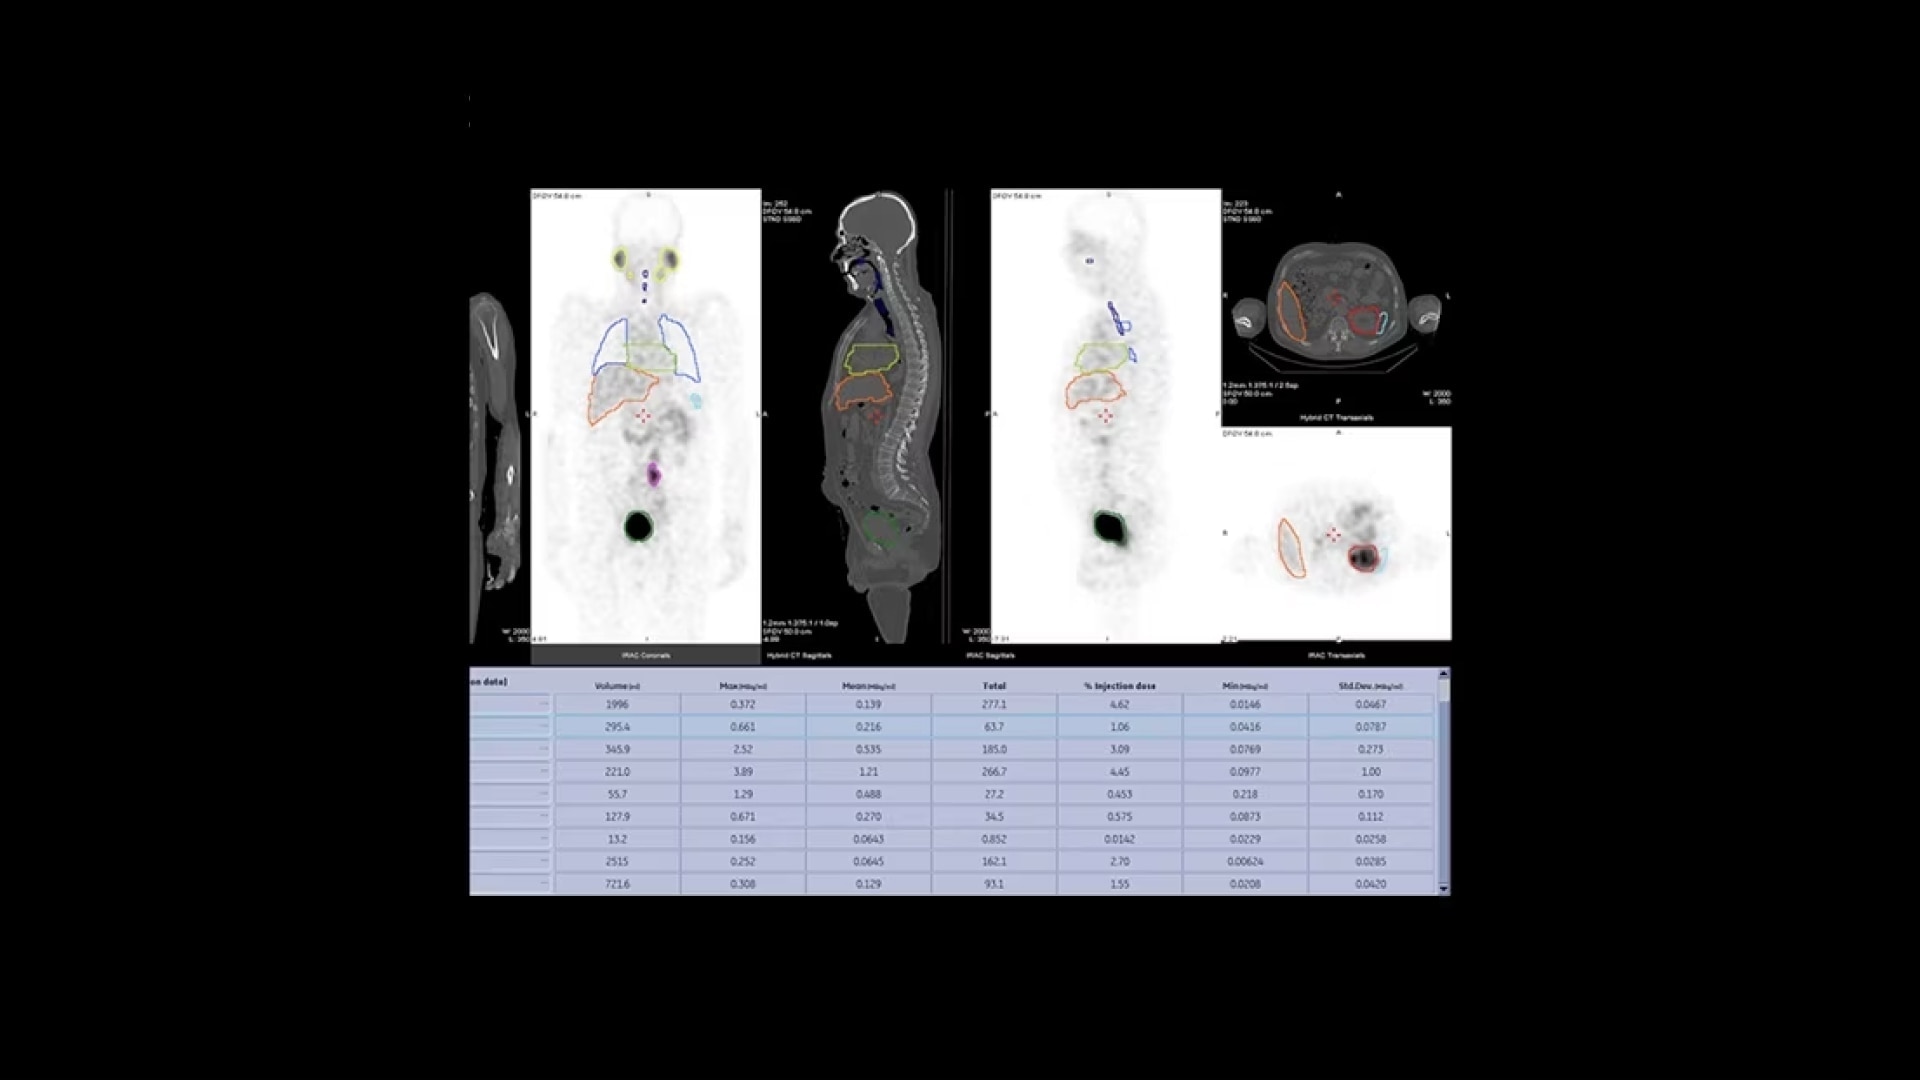

Additionally, this is a premium SPECT/CT system that delivers the added flexibility of a standalone CT that includes advancements in dose and metal artifact reduction. And it delivers the accurate, reproducible results referring physicians require in a comfortable and streamlined exam experience.